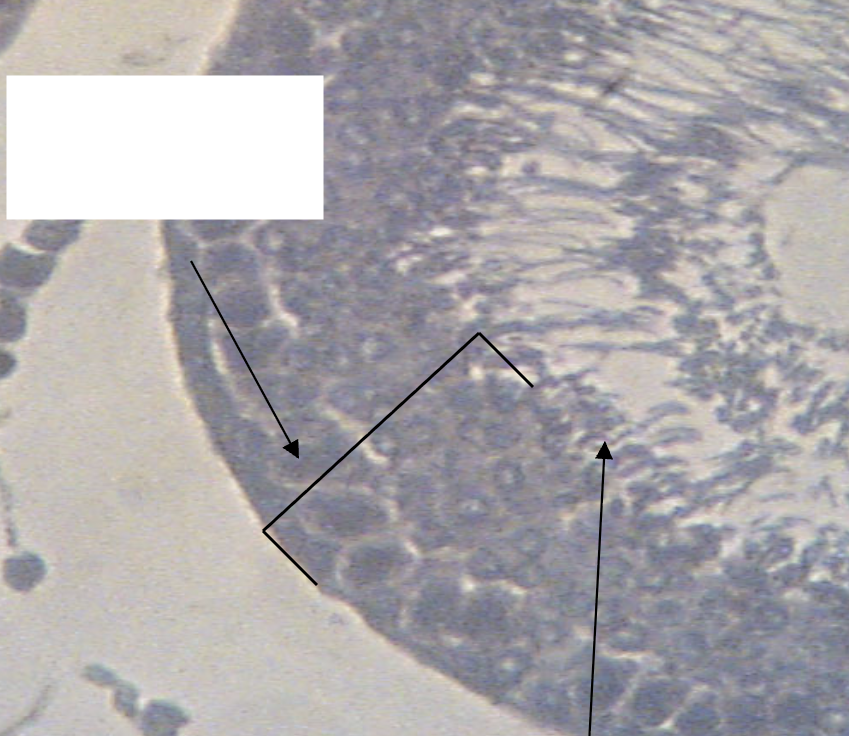

Seminiferous tubules

What structure is being depicted in this cross section?

Testis

What structures are being indicated by #1?

Sertoli cells

What structure is being indicated by the white circle?

Lumen

Leydig cells